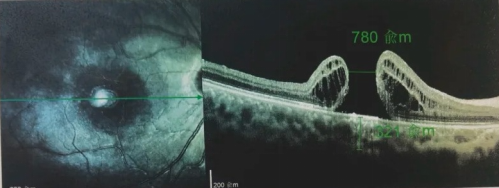

由于自身患有頸椎病,每次術(shù)后長(zhǎng)期的趴睡都讓他痛苦不堪。為了尋求更好的治療,吳爺爺來到廈門大學(xué)附屬?gòu)B門眼科中心,找到了眼外傷及眼底病2科的李海波博士后。此時(shí),吳爺爺右眼的黃斑裂孔已經(jīng)持續(xù)擴(kuò)大到780μm,演變?yōu)殡y治性的大裂孔。

最讓吳爺爺難以置信的是:術(shù)后只需保持平躺24小時(shí)!第二天復(fù)查時(shí),眼底鏡及OCT檢查清晰顯示——那個(gè)折磨了他大半年的大裂孔,竟然閉合了!且吳爺爺?shù)挠已垡暳τ辛嗣黠@的改善,術(shù)后3天已經(jīng)可以看到 0.15。